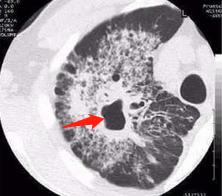

4.磨玻璃密度影:

肺结核的间质损伤,可以呈磨玻璃密度改变:

右下肺干酪性肺炎,形成空洞,周围大片磨玻璃影